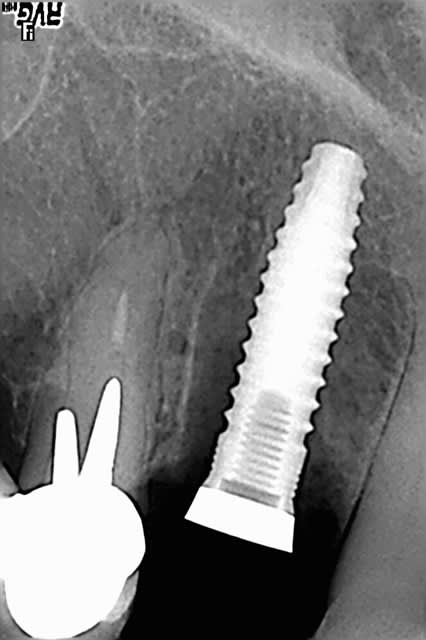

Voila, tout est dans le titre, une patient avec une dent re-implanté suite accident de voiture en 1990. Resorption externe et semble ( comme la 12 ) completement ankylosée.

je tenterais bien une EII avec un implant de 13 mm ø 4 mini plus mise en vitrine et biomat', mais ça dépendra de l'état de l'alvéole après ton extraction; les ankyloses, ce n'est pas de la tarte, et si tu perds en plus le pan vestibulaire de l'alvéole....

Une EII, tres bien, mais tu le dis toi-même, tout dépend de l'extraction, sachant qu'en plus, il y a un sourire gingivale, faut pas se louper.

Je pense en fait bouffer la dent a la fraise pour economiser l'os alvéolaire, car si l'on part sur de l'alvéoltecmie, on se dirige plutot vers une greffe ensuite, non ?

J'aimerai bien, en fait savoir a l'avance ce que je vais faire, et pouvoir l'expliquer a la patiente. Bien sur, on peut etre amener a modifier un plan de ttt au cour d'un acte, mais dire" je vais extraire, si je peux, et on verra bien si je met l'implant" me parait un peu leger.

Si je fraise la dent, puis je passe mes forets et pose l'implant, c'est grave, docteur si j'ai oublié des bouts de dent ? ( la limite dent-os est pas toujours évidente, même si l'os, ça saigne et pas la dent ).